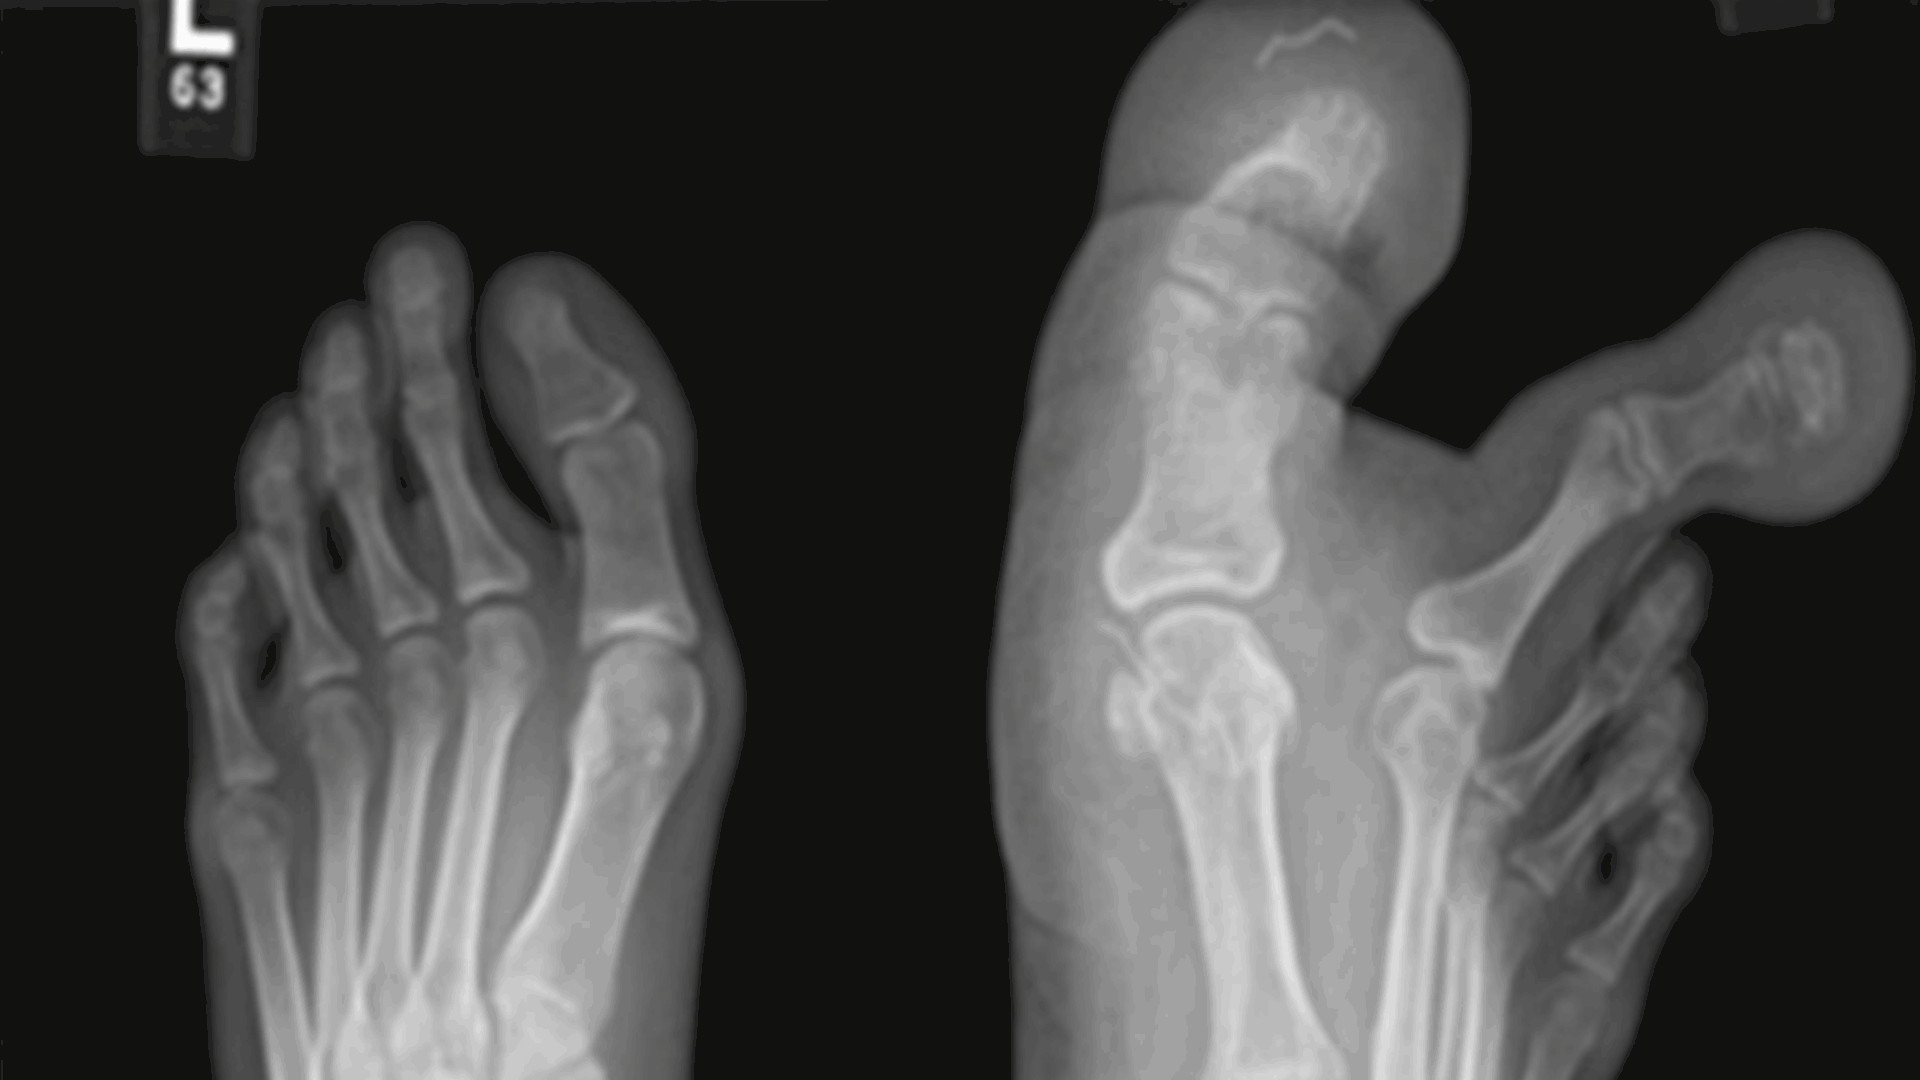

لم تكن قادرة على ارتداء الأحذية وتواجه صعوبة بالمشي... إبنة الـ12 سنة عانت كثيرا والسبب: أصابع قدمها العملاقة! (صور)

نشر الأطباء صوراً لرجل فتاة ولدت بإصبعين عملاقين في قدمها.

وتم تشخيص حالة الطفلة البالغة من العمر 12 عامًا بأنها مصابة بالحثل الشحمي الكبير (MDL)، وهو عيب خلقي يتسبب في توسع العظام والأنسجة والأعصاب في إصبع القدم الكبير والثاني في قدمها اليمنى.

"عملقة" الفتاة التي لم يذكر اسمها جعلت من الصعب عليها المشي وارتداء الأحذية.

وتم تشخيص التشوه لدى المريضة عند ولادتها، لكنها لم تحضر زيارة متابعة للأطباء منذ ذلك الحين.

وطلب والداها، اللذان يعيشان في العاصمة الماليزية كوالالمبور، المساعدة عندما تفاقم تشوه قدم ابنتهما، وفق ما نقل

ذا صن

.

وقال الدكتور سري أرون سيلفام، جراح العظام في المركز الطبي بجامعة كيبانجسان: "كشفت الصور الشعاعية البسيطة ونتائج التصوير بالرنين المغناطيسي عن تراكم الأنسجة الدهنية حول إصبع القدم الأول والثاني، والجوانب الوسطى والجانبية لمشط القدم الأول، وتمتد حتى القوس الأخمصي الأوسط للقدم."

وتابع: "إن MDL هو نوع غير شائع جدًا من العملقة الخلقية الموضعية، وغالبًا ما يتم إجراء الاستشارة الجراحية لأسباب تجميلية."

ولتحسين وظيفة القدم، أجرى الفريق الطبي عملية إعادة بناء ناجحة.

وبسبب هذا، تستطيع الطفل الآن ارتداء الأحذية والمشي بشكل صحيح.

وعادة ما يحدث الحثل الشحمي الكبير بشكل عشوائي وليس أمرا وراثيا.

ويمكن أن يتم تشخيصه بشكل خاطئ على أنه ورم ليفي عصبي، وهي أورام حميدة نادرة وبطيئة النمو في العصب المحيطي.